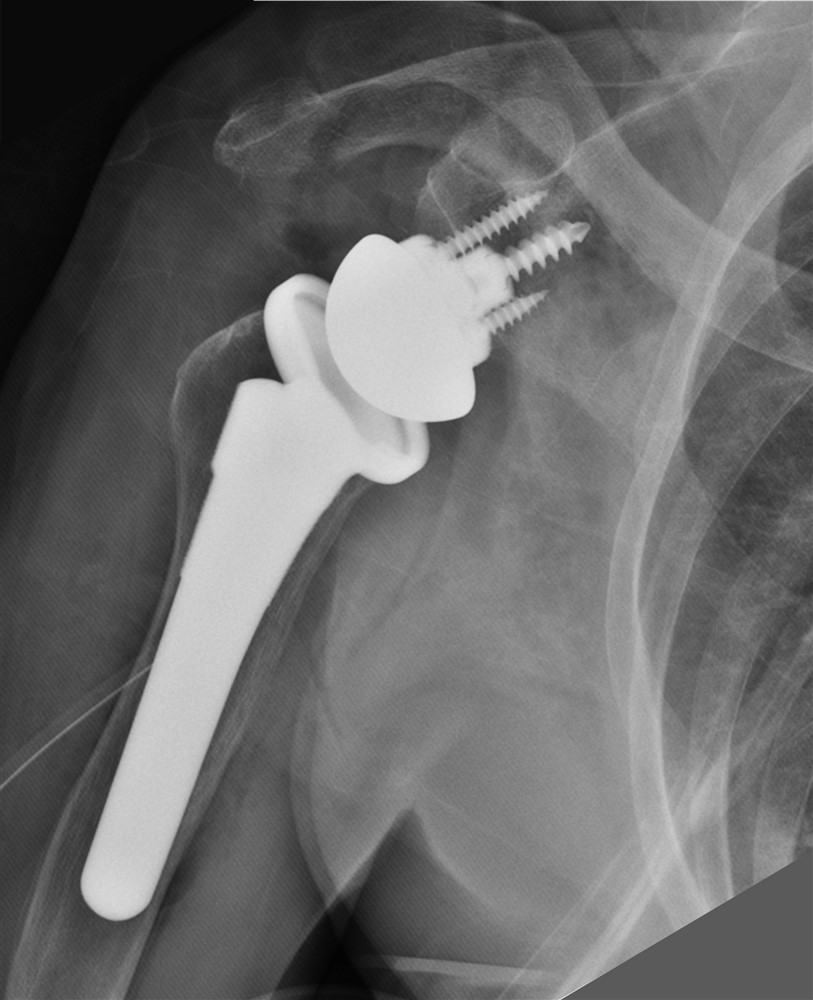

反置式人工肩關節置換手術,有效幫助病人恢復肩部的活動能力。

旋轉肌袖破裂病人接受反置式人工肩關節置換手術後獲得改善。

經謝尚霖醫師門診檢查診斷為「右肩大片旋轉肌袖破裂合併肩關節軟骨磨損」,因為旋轉肌腱斷裂面積大而且肌肉組織都已嚴重脂肪性變化,以致無法修補。肩關節炎軟骨磨損確實會造成疼痛,病人在醫師建議下接受「反置式人工肩關節置換手術」,手術後肩關節疼痛明顯改善,也持續接受復健療程。肩關節活動度持續恢復,睡眠狀況變好,生活品質也大幅提升。

新型「反置式人工肩關節置換手術」,藉改變人工關節假體設計與截骨的方式,將原本球形的肱骨頭改成圓盤狀,原本圓盤狀的肩胛盂改成半球狀。讓三角肌能更有效率抬舉手臂,避開破損的旋轉肌袖。反置式人工肩關節置換手術也能幫助其他如老年人創傷性肩關節複雜骨折、肩關節類風濕性關節炎、旋轉肩肌袖大破裂合併肩關節退化、先前肩關節置換手術後併發症、或近端肱骨腫瘤等病人。